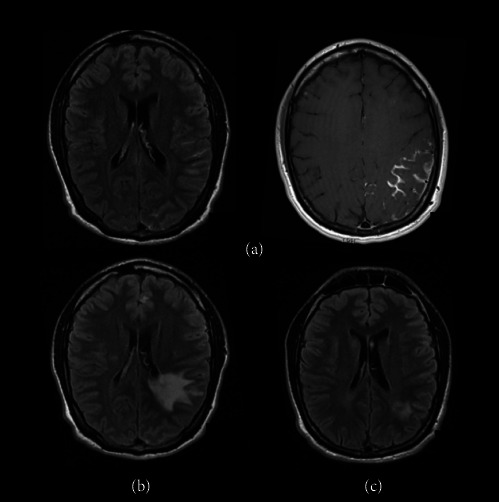

前言:结核治疗期间的矛盾反应的特点是先前存在的结核病变的临床或放射学恶化,或在适当的TBC治疗后出现新的表现。识别这种现象是至关重要的,因为它可能被误认为是治疗失败或复发。尽管在免疫重建炎症综合征后的HIV患者中有广泛的报道,但关于HIV阴性患者的文献很少。病例系列:我们报告了三例免疫功能正常的中枢神经系统结核(CNS-TBC)患者,他们在适当的TBC治疗后出现了矛盾反应。这些包括不同的临床和放射表现,如持续性头痛、结核瘤的出现或进展、脑梗死和脊髓炎。从抗tbc治疗开始平均2.5个月内发生矛盾反应。结论:我们的研究结果强调了密切监测抗tbc治疗后患者的重要性,以迅速发现潜在的并发症。在进行彻底的鉴别诊断时,应考虑到对结核分枝杆菌复合体抗原的过度免疫反应引起的矛盾反应,包括其他中枢神经系统感染、肉芽肿或肿瘤疾病、治疗失败或治疗相关毒性。在这种情况下,确保充分坚持抗tbc治疗和免疫抑制剂至关重要。

Introduction: Paradoxical reactions during tuberculosis (TBC) therapy are characterized by clinical or radiological worsening of preexisting tuberculous lesions or the appearance of new manifestations following appropriate TBC treatment. Identifying this phenomenon is crucial, since it can be mistaken with treatment failure or relapse. Although widely described in HIV patients following immune reconstitution inflammatory syndrome, the literature on HIV-negative patients is scarce. Case Series: We present three cases of immunocompetent patients with central nervous system tuberculosis (CNS-TBC) who developed paradoxical reactions following appropriate TBC therapy. These included diverse clinical and radiological manifestations, such as persistent headaches, apparition or progression of tuberculomas, cerebral infarcts, and dorsal myelitis. Paradoxical reactions occurred within an average of 2.5 months from the start of anti-TBC treatment. Conclusion: Our findings underscore the importance of closely monitoring patients following anti-TBC treatment to identify potential complications rapidly. Paradoxical reactions due to exaggerated immune response to Mycobacterium tuberculosis complex antigens should be considered in a thorough differential diagnosis including other CNS infections, granulomatous or neoplastic disorders, treatment failure, or treatment-related toxicities. Ensuring adequate adherence to anti-TBC treatment and immunosuppressants is essential in such cases.